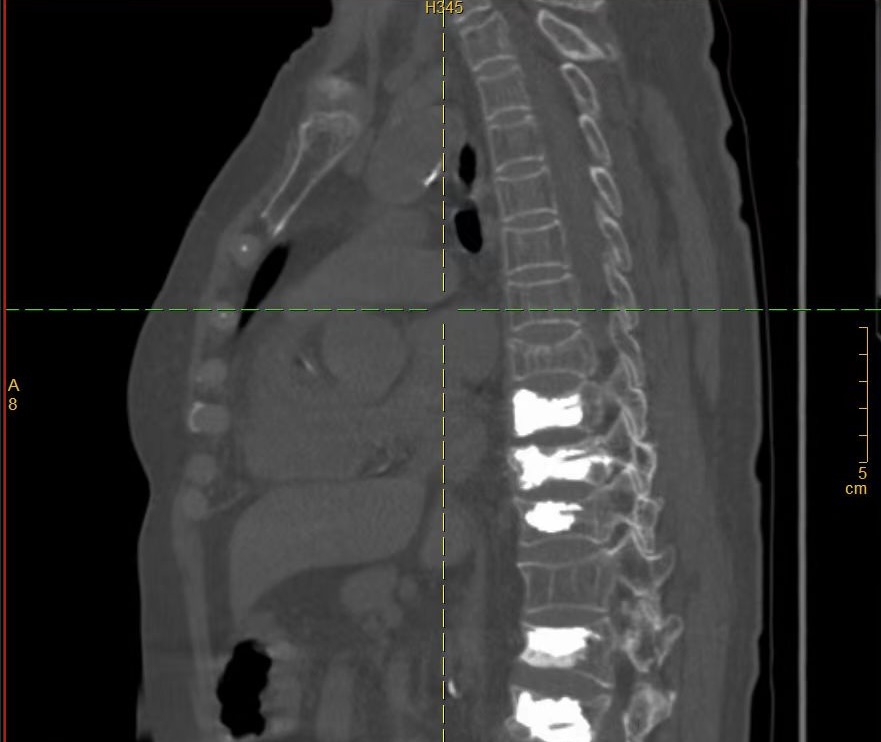

术前CT

“做完手术就能下床走路,真是太感谢你们了!” 近日,在我院骨一科病房,赵奶奶握着医护人员的手,激动地说道。赵奶奶是一位重度骨质疏松患者,近年来饱受腰背疼痛的折磨,曾多次来我院接受骨水泥治疗。近日,赵奶奶不慎闪腰,导致胸背部剧烈疼痛,难以忍受,遂来我院骨一科就诊。经检查,赵奶奶被诊断为胸7椎体压缩性骨折。